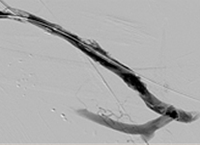

xray image of liac vein post-PTA & stent.

Iliac vein post-PTA & stent